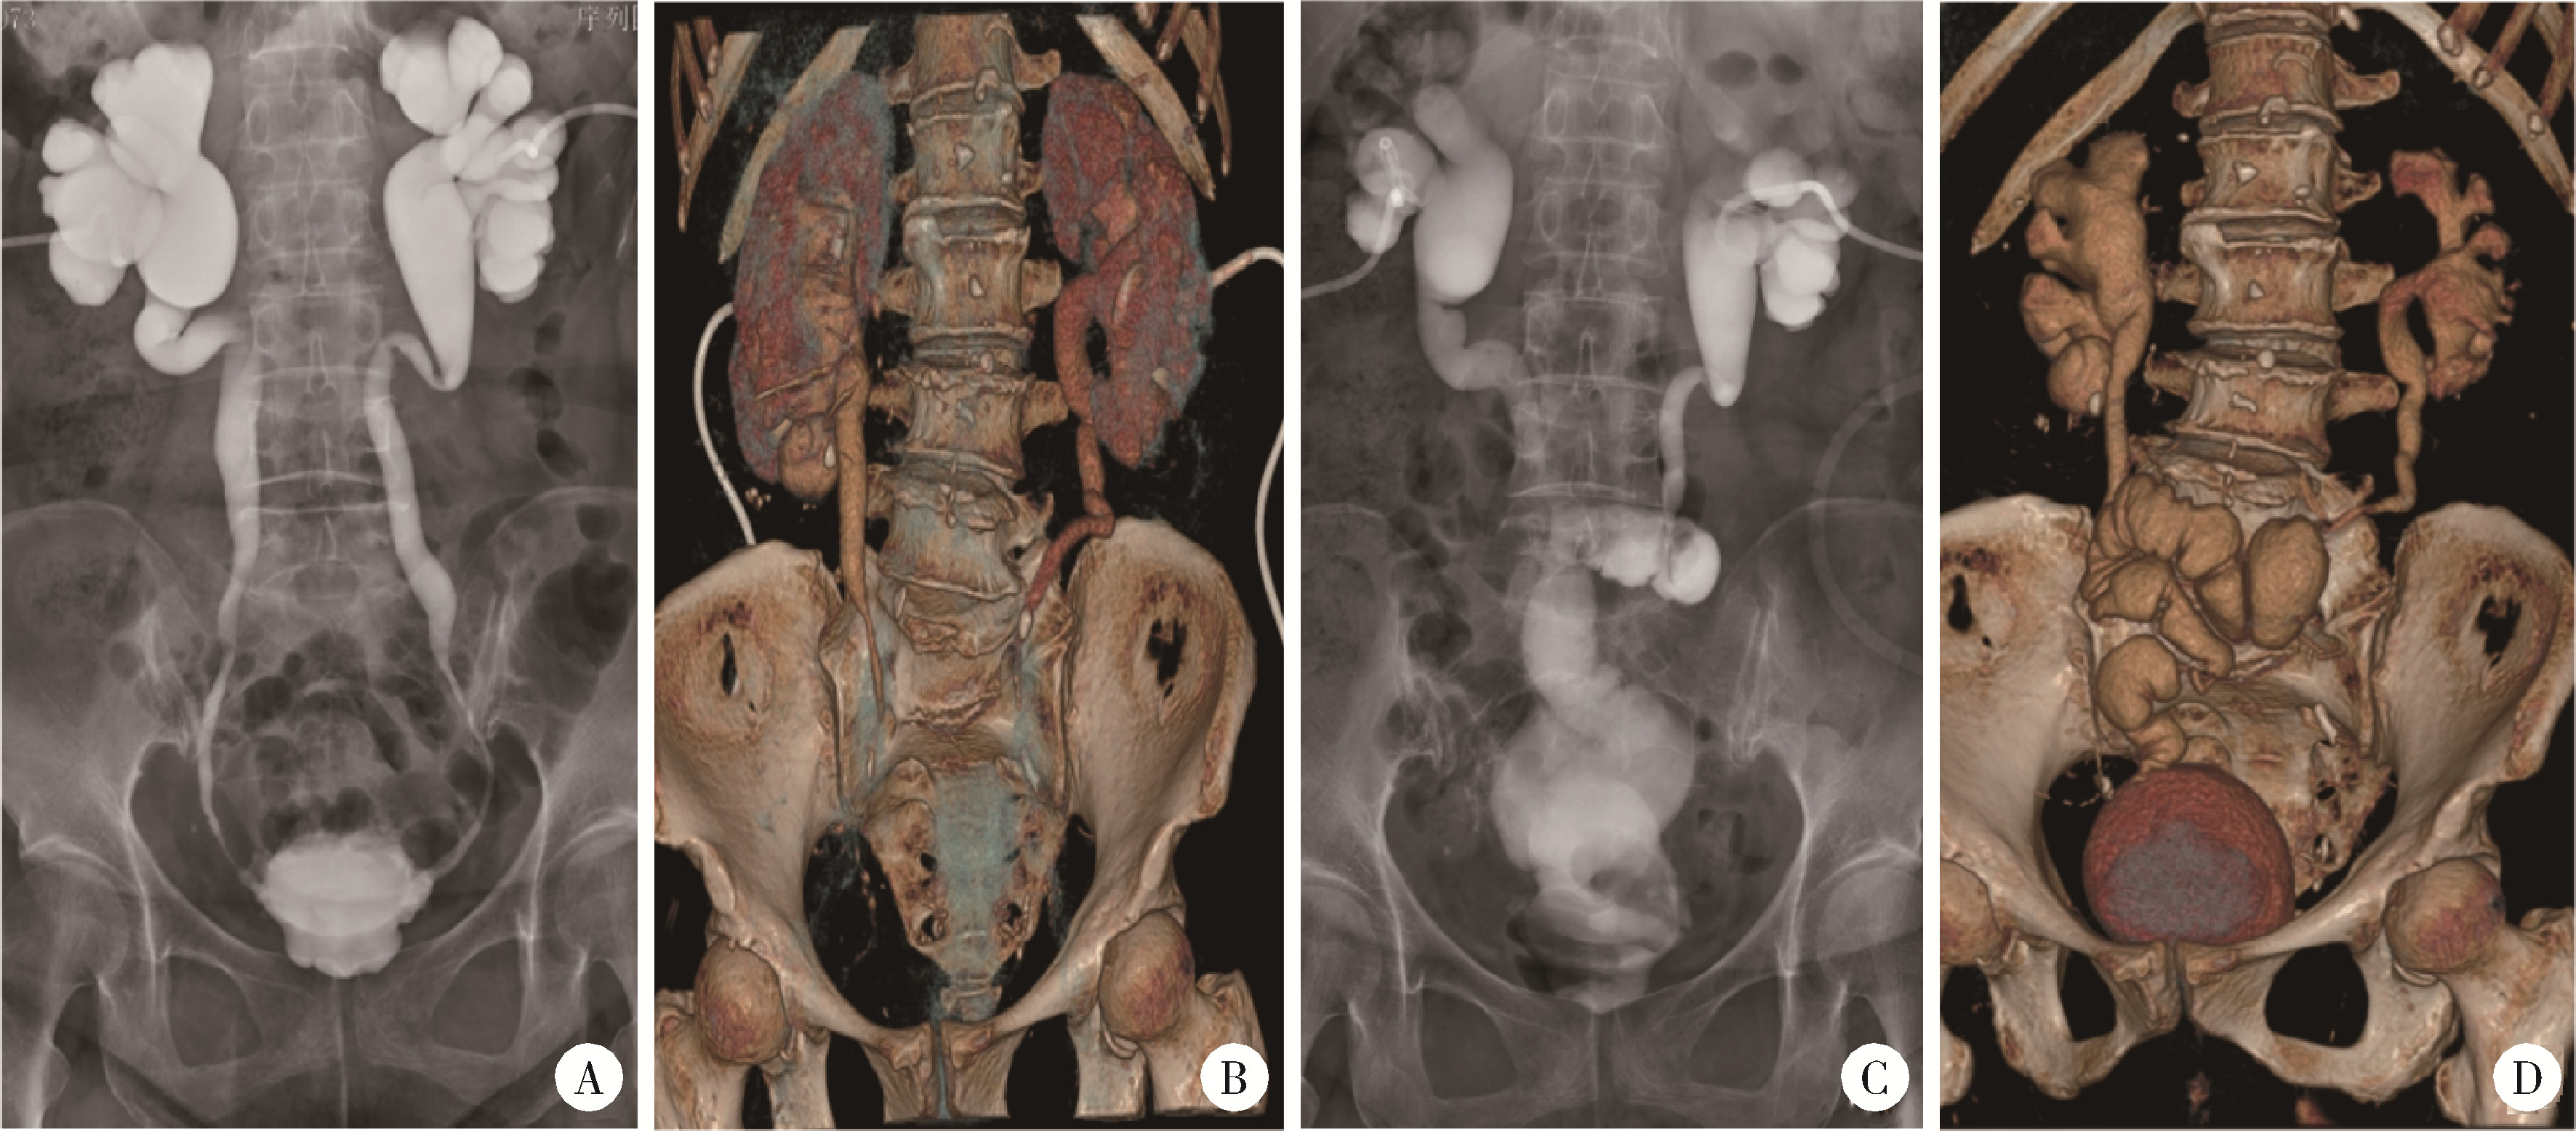

Figure 3

Preoperative and postoperative imaging examinations A and B, preoperative nephrostogram and 3D CT reconstruction demonstrated bilateral long-segment ureteral strictures, contracted bladder with reduced capacity, and rigid, thickened bladder walls; C and D, two-month follow-up 3D CT reconstruction revealed good peristalsis in the ileal ureteral substitute segment. The bladder exhibited symmetrical morphology with smooth wall contour."